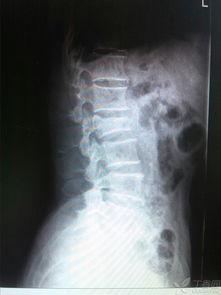

腰椎骨折可不是闹着玩的,这可是个严重的健康问题。下面,我们就请专家来为大家解读一下腰椎骨折的危害。

1. 疼痛:腰椎骨折会导致剧烈的疼痛,让人难以忍受。

2. 活动受限:骨折后,患者可能无法正常活动,甚至无法站立。

3. 并发症:腰椎骨折还可能引发其他并发症,如神经损伤、感染等。

4. 影响生活:长期卧床会导致肌肉萎缩、关节僵硬等问题,严重影响生活质量。